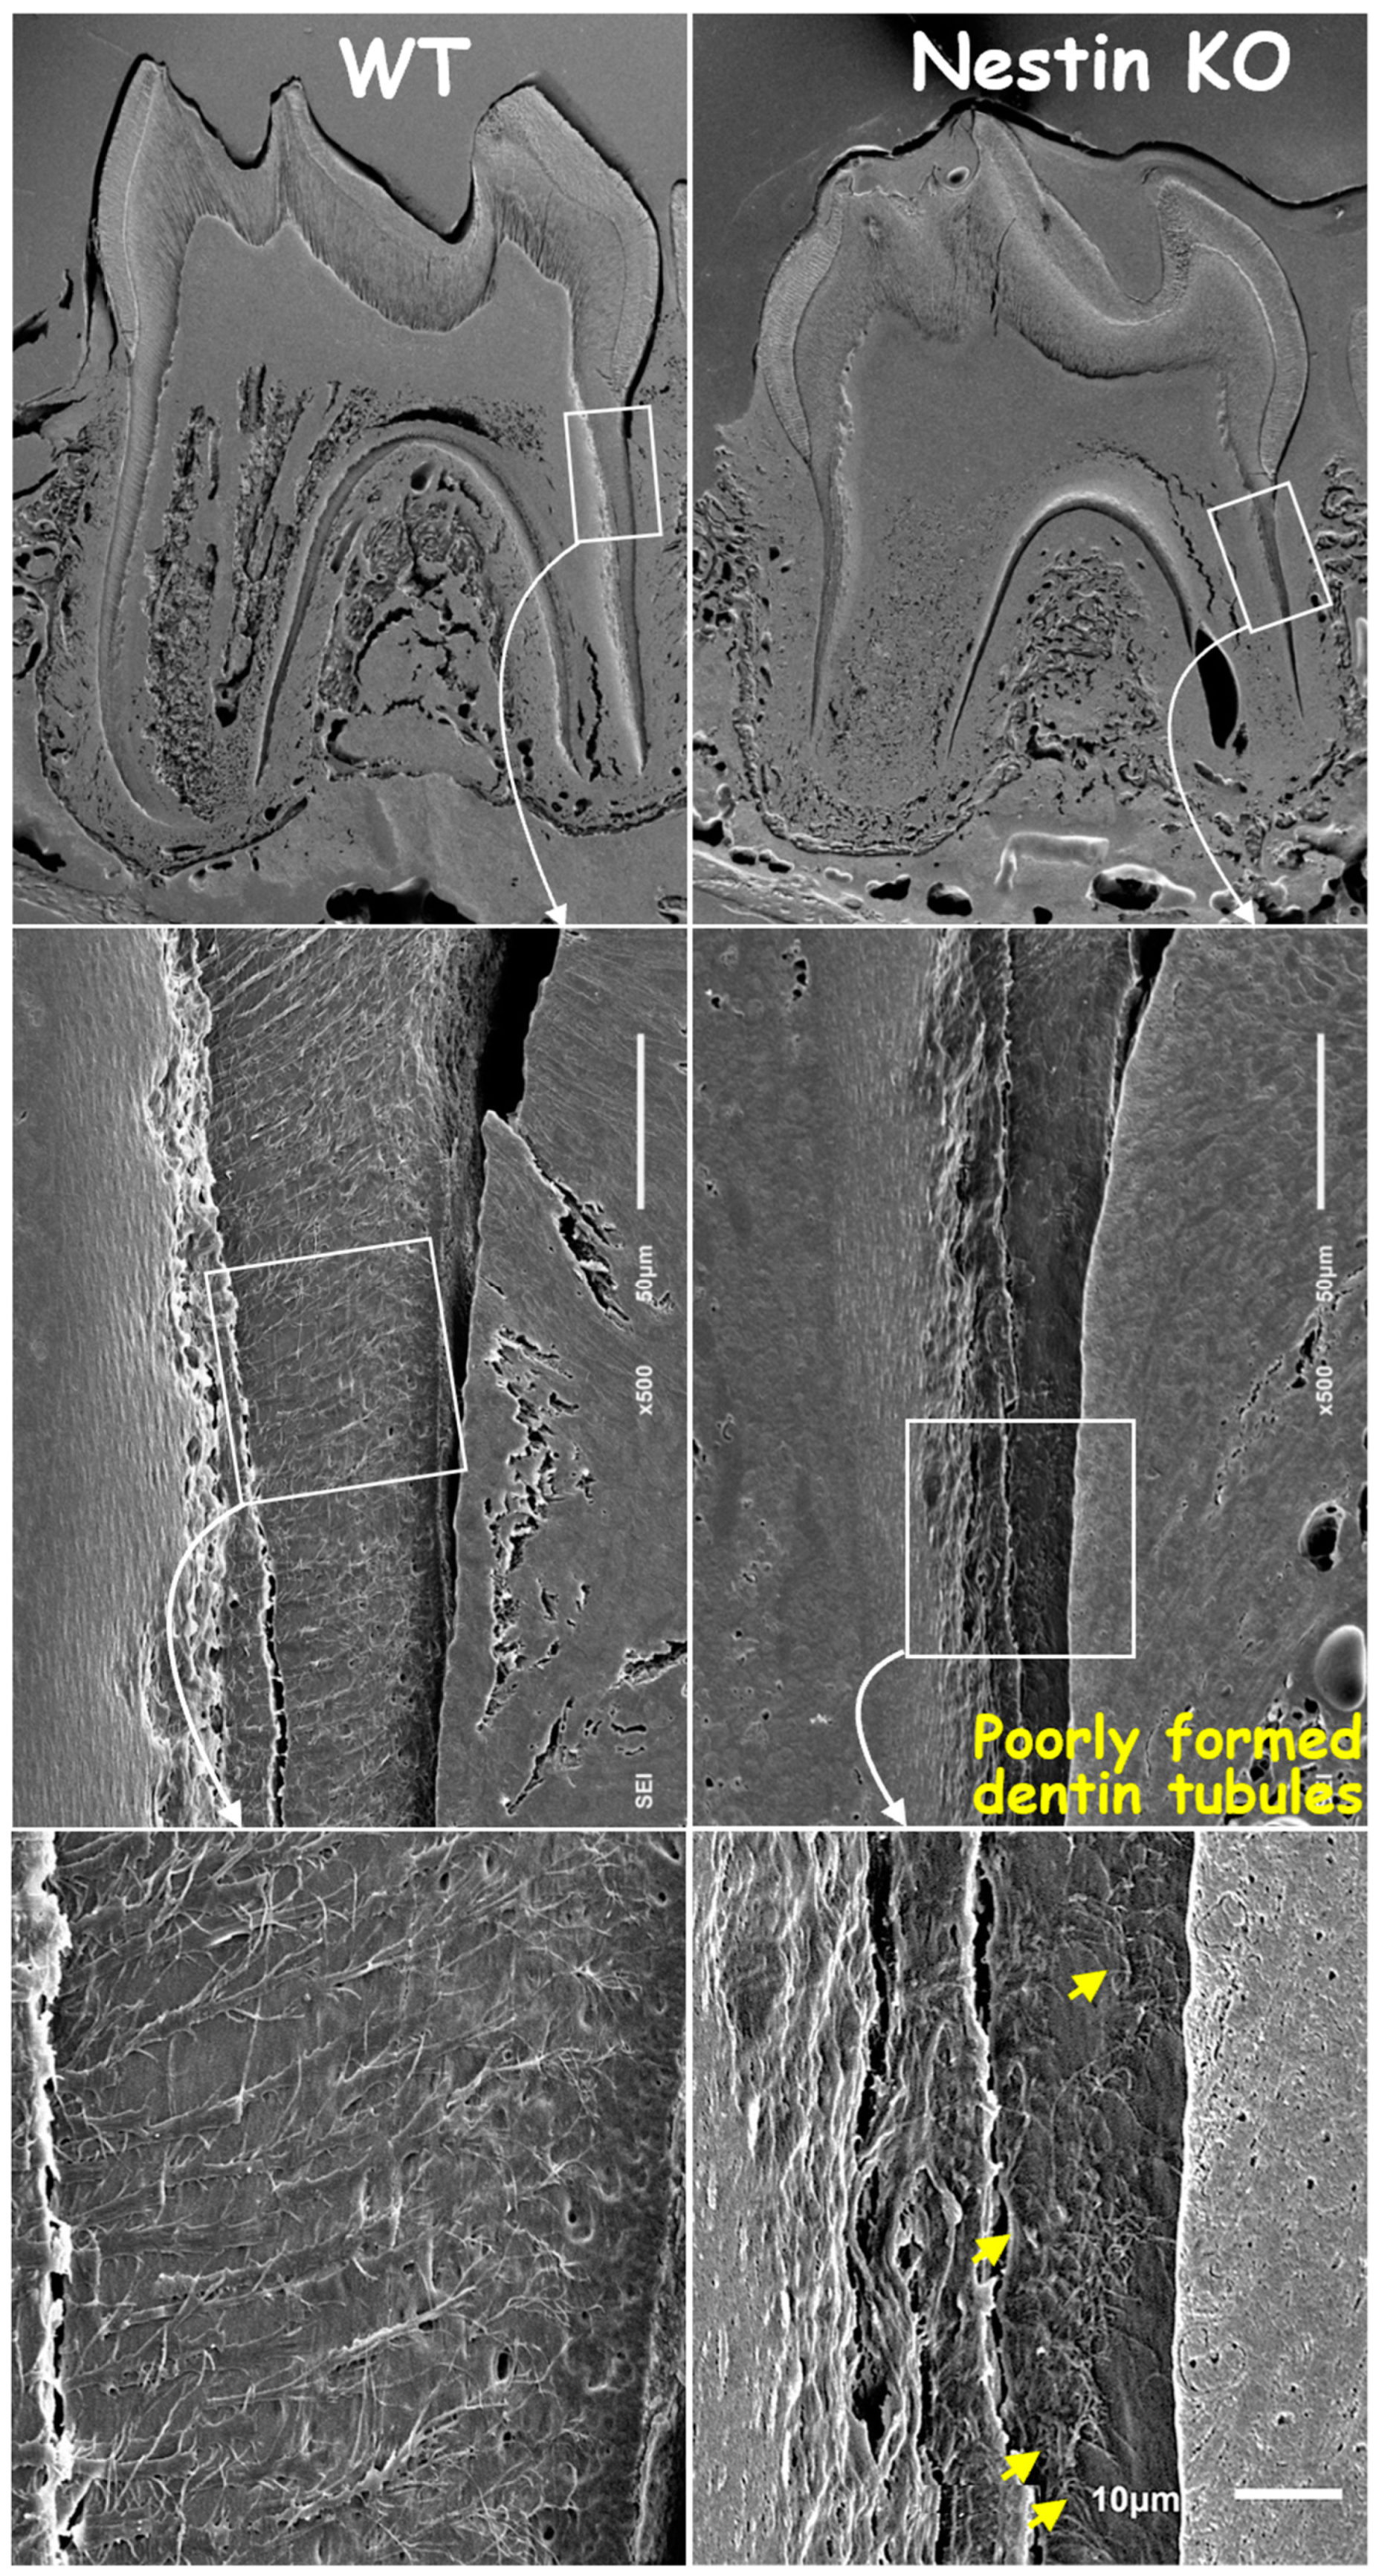

3.2. Nestin KO Mice Displayed Malformed Dentin Tubules in Roots